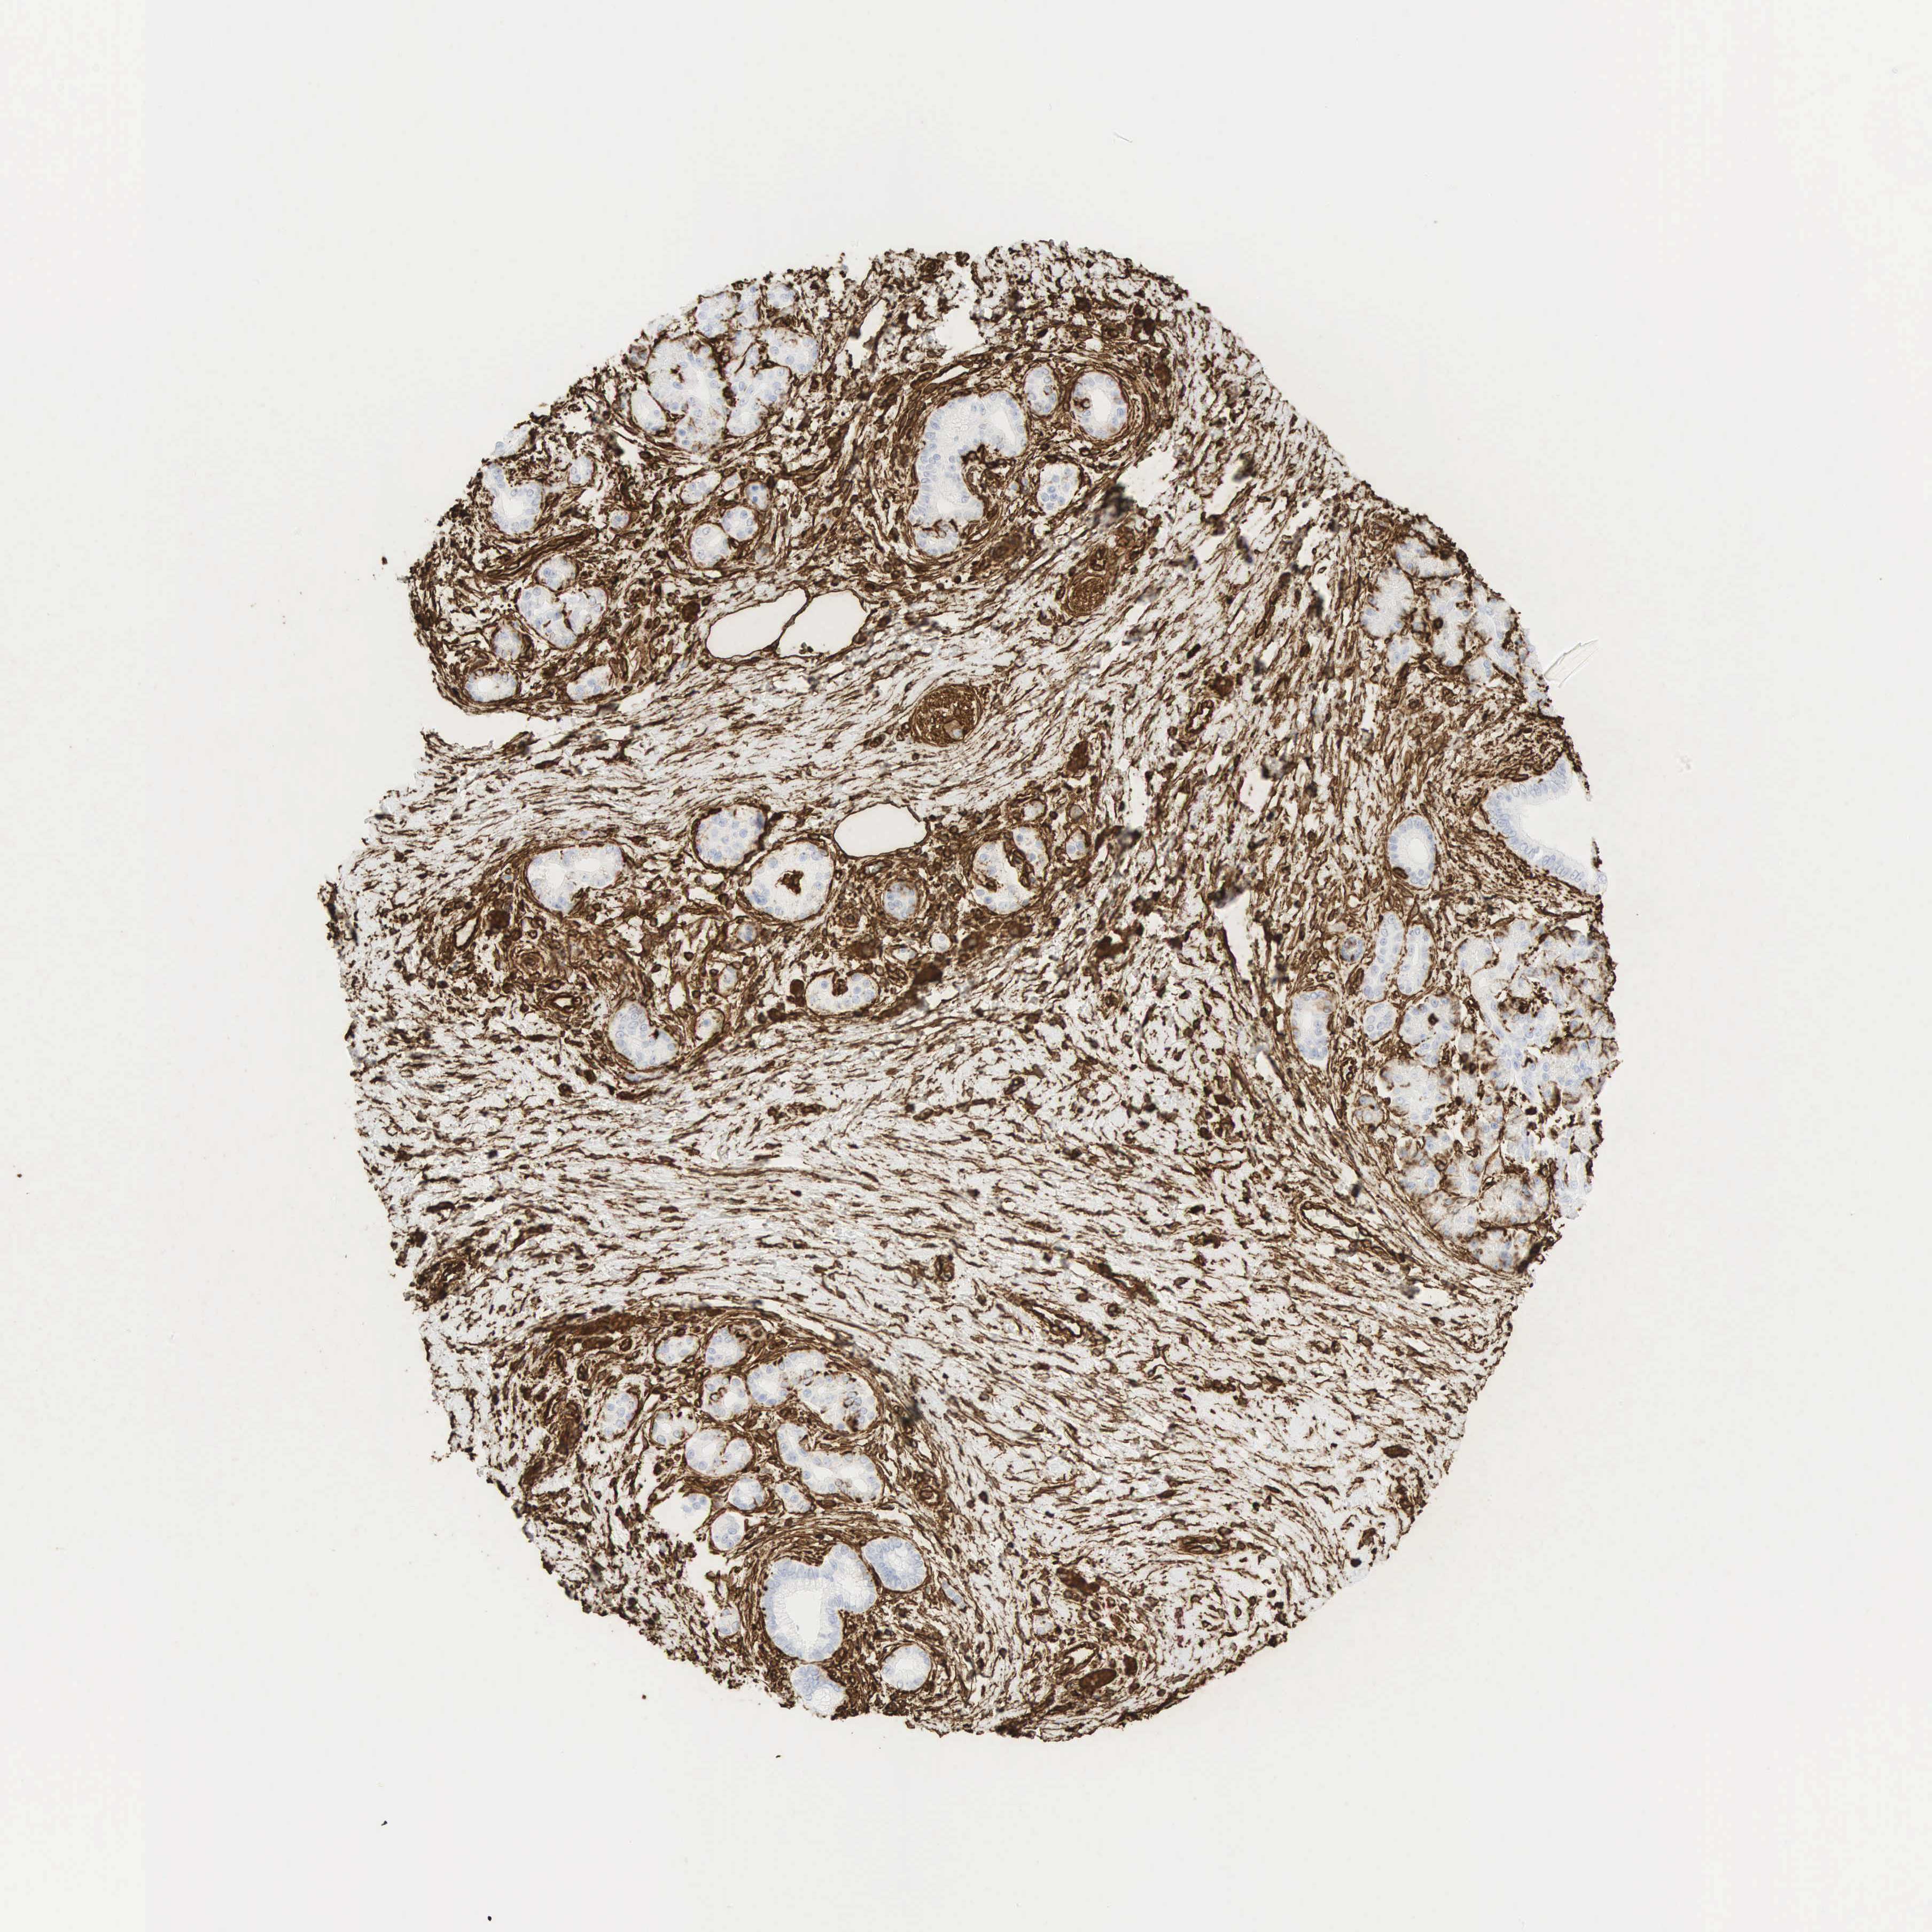

PANCREATIC CANCER - Protein expressioni

A mouse-over function shows sample information and annotation data. Click on an image to view it in a full screen mode. Samples can be filtered based on level of antibody staining by selecting one or several of the following categories: high, medium, low and not detected. The assay and annotation is described here.

Note that samples used for immunohistochemistry by the Human Protein Atlas do not correspond to samples in the TCGA dataset.

Antibody stainingi

Antibody staining in the annotated cell types in the current human tissue is reported as not detected, low, medium, or high, based on conventional immunohistochemistry profiling in selected tissues. This score is based on the combination of the staining intensity and fraction of stained cells.

Each image is clickable and will lead to virtual microscopy that enables deeper exploration of all samples and also displays staining intensity scores, fraction scores and subcellular localization as well as patient and tissue information for each sample.

Antibody HPA001762

Antibody CAB000080

Antibody CAB058687

Staining

High

Medium

Low

Not detected

Intensity

Strong

Moderate

Weak

Negative

Quantity

>75%

75%-25%

<25%

None

Location

Nuclear

Cytoplasmic/membranous

Cytoplasmic/membranous,nuclear

Adenocarcinoma, NOS

Adenocarcinoma, metastatic, NOS